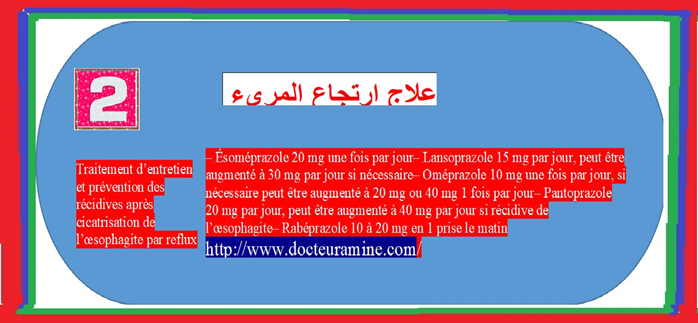

تحتل أدوية م م ب المحل الرئيسي في أخذ موقف علاج حالة الارتجاع المعدي المريئي. يبات ا م م أقل حموضة وبالتالي أقل تسمما للغشاء المخاطي المريني (13) الأمر الذي يؤول الى سرعة التئام الآفات أو جروح الالتهابات المريئية (14). بجانب تحقيق وتراجع الأعراض الناجمة عن الارتجاع المعدي المريئي يتم اللجوء الى تناول م م ب . بجانب تحقيق وتراجع اعراض الناجمة عن الارتجاعي المعدي المريئي. يتم اللجوء لتناول م م ب قصد التئام التهاب المريء الناجم عن حالة الترجيع المعدي المريئي للوقاية ضد الانتكاسات التي تبرز بعد التئام الجراح بجانب علاج حالة الجزر المعدي المريئي الذي تخلفه عقاقير ا م م البروتون التميز بالأعراض السريرية و وجود الدم في البراز. تختلف الجرعات الموصي بها حسب وجود أو عدم التهاب المريء. يلخص جدول رقم 1

توصف م م ب جرعة كاملة (17). بينما نكتفي بأربعة أسابيع لعلاج التهاب المريء الغير شديد ومن أجل الوقاية بواسطة مم ب جرعة كاملة أو نصف الجرعة تصديا للانتكاسات

وفق ترتيب لوس إنجليس في حالة الغشاء المخاطي باريت (28) ، شرط أن يضاف اليها اما أعراض و/أو اصابات التهاب المريء . و في حالة ا م م الموثق (29) و الذي يستجيب للعلاج بدون م م ب و وفق تلك المؤشرات، يستجيب وصف م ةم ب بأدنى جرعة فعالة. أم الاستمرار في تناولها فيتطلب المناقشة.